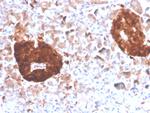

NSE gamma (Neuron Specific Enolase, gamma) (Neuroendocrine Marker) Antibody in Immunohistochemistry (Paraffin) (IHC (P))

NSE gamma (Neuron Specific Enolase, gamma) (Neuroendocrine Marker) Antibody (2026-MSM7-P0) in IHC (P)

Formalin-fixed, paraffin-embedded human pancreas stained with NSE gamma Mouse Monoclonal Antibody (ENO2/4507). {{ $ctrl.currentElement.advancedVerification.fullName }} 验证信息 View more